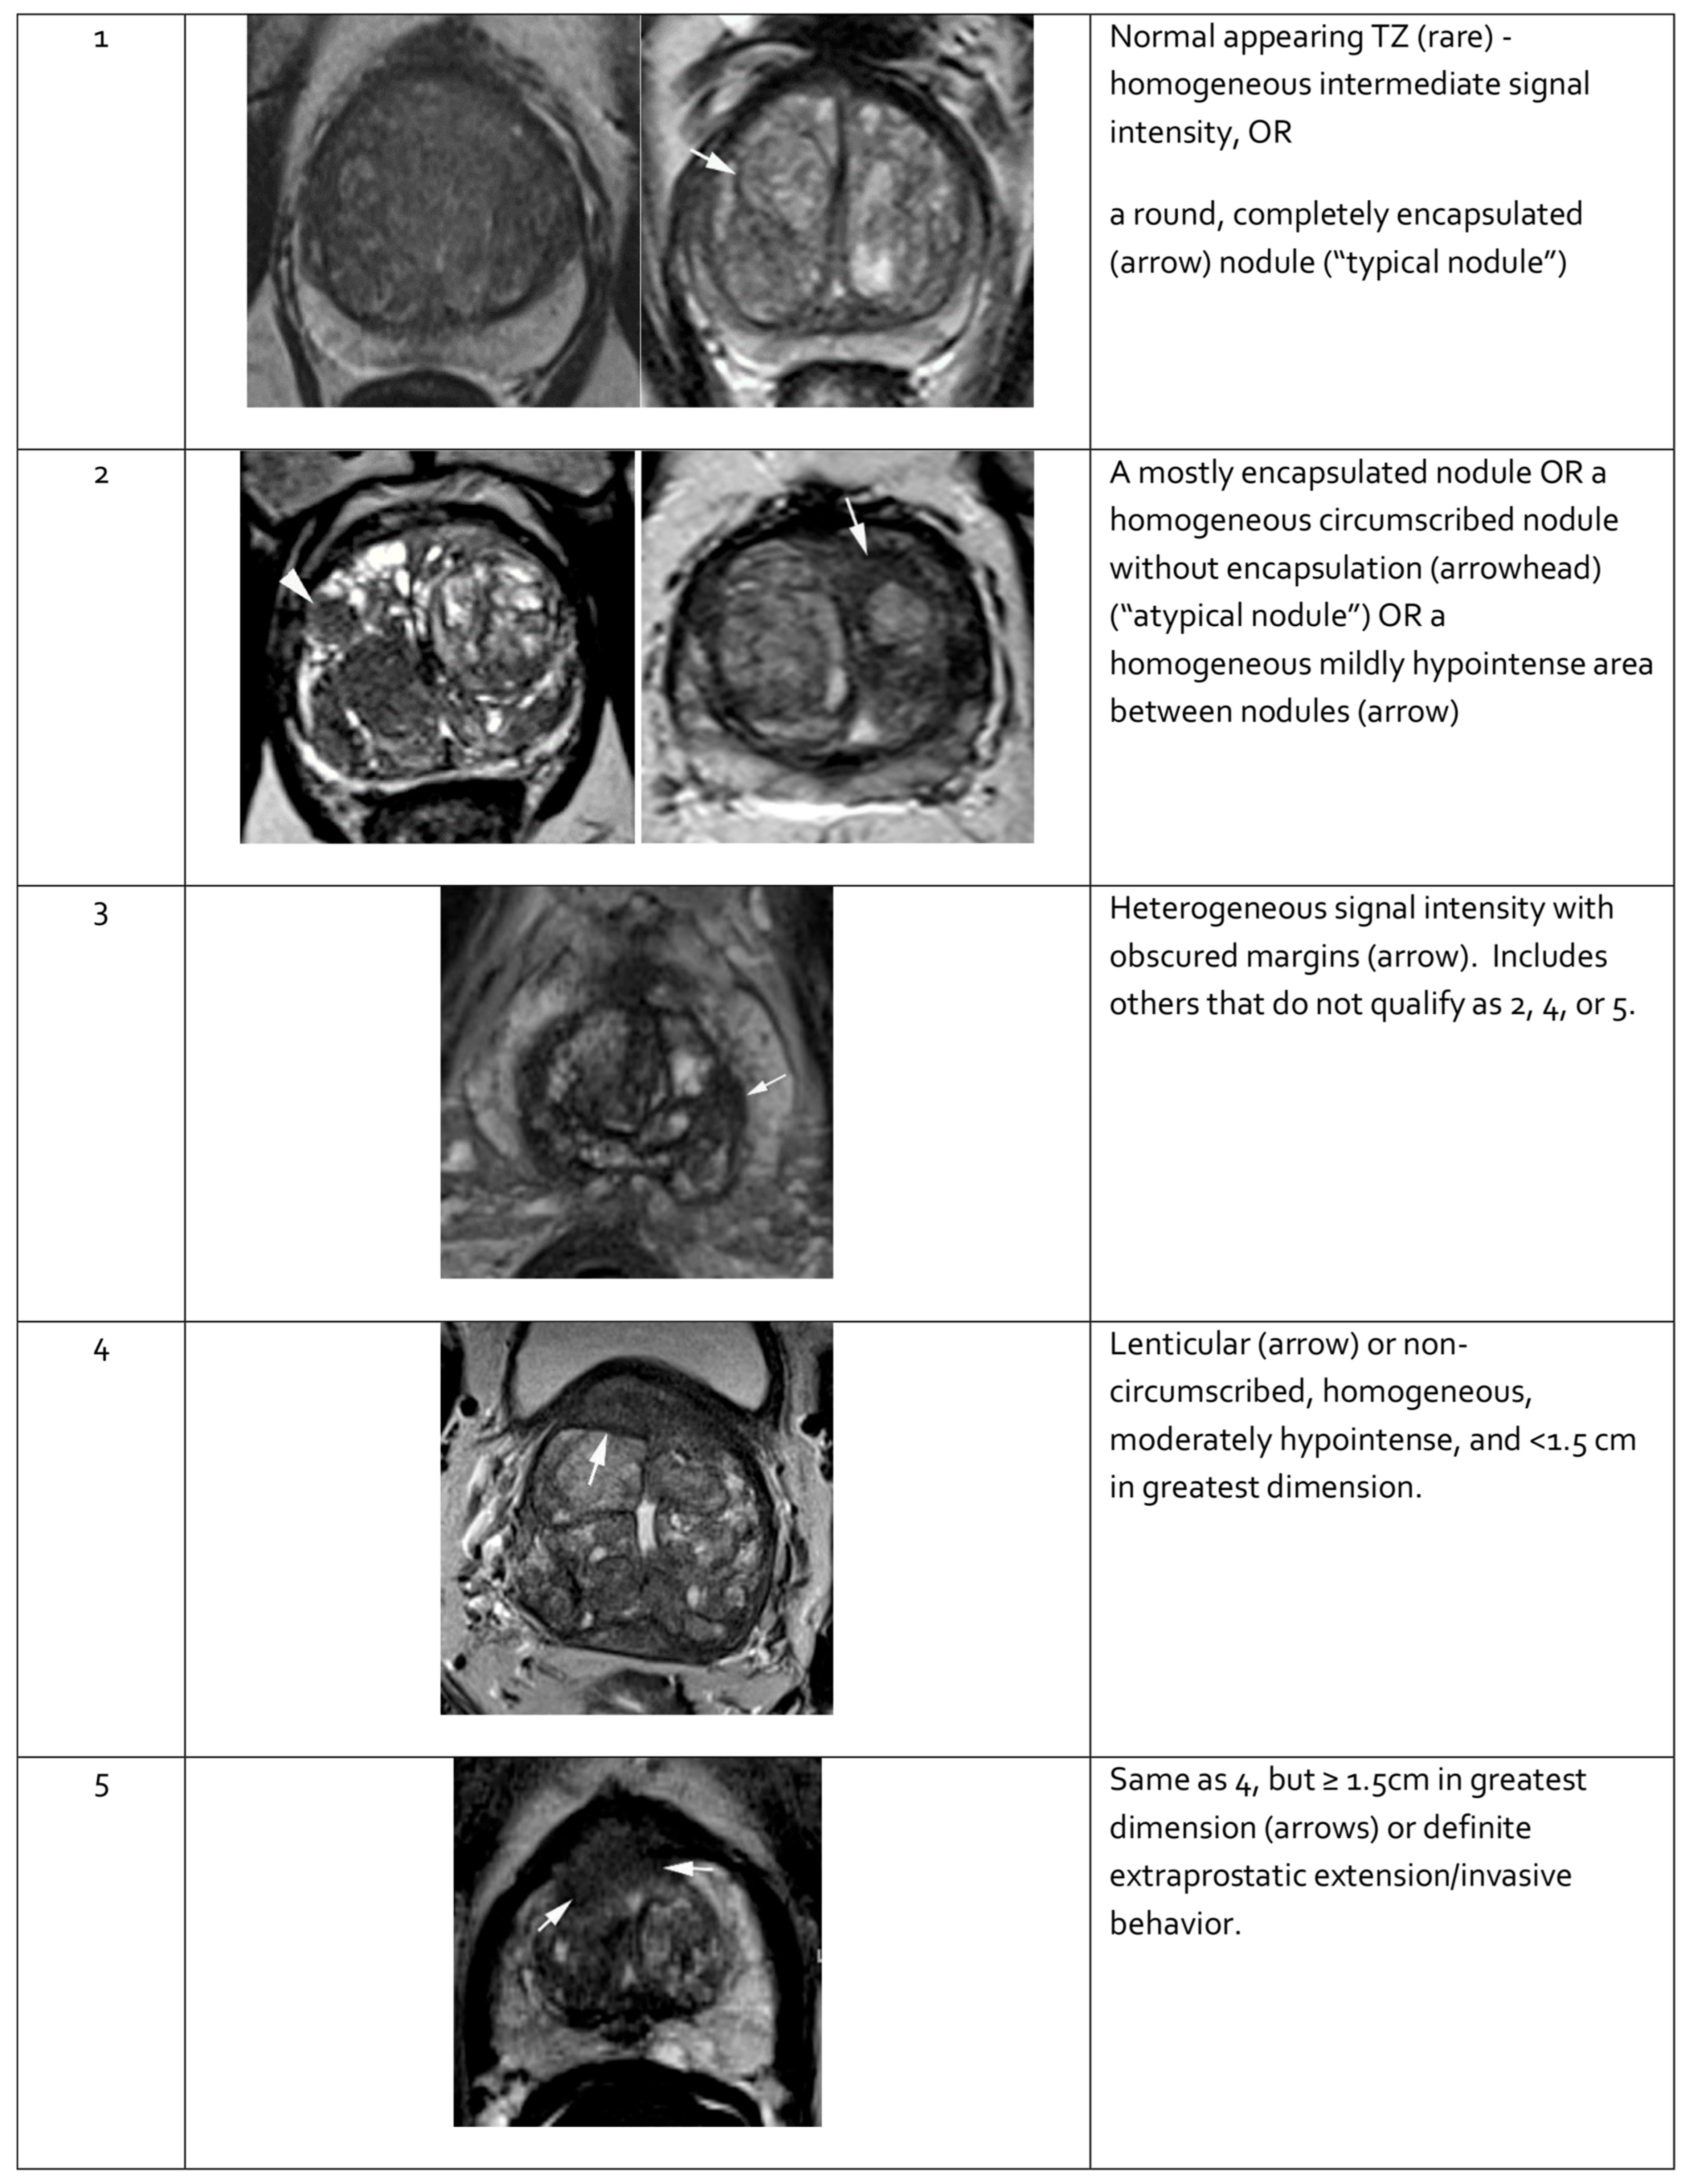

When evaluating a lesion detected by mpMRI, its anatomical location is critical. T2-weighted images are most informative for lesions in the transition zone, while DWI is dominant for assessing the peripheral zone. Lesion measurements should be performed using the most informative imaging sequence for the specific prostate zone. Representative mpMRI images corresponding to PI-RADS scores are shown in Figure 3 and Figure 4. mpMRI is more effective in detecting clinically significant PCa lesions in the peripheral zone than in the transition zone. Given the growing number of mpMRI examinations, there is a trend toward simplifying protocols by omitting DCE. DCE plays a relatively minor role in primary PCa diagnosis and is associated with potential side effects, longer procedure time, and higher cost [95]. The role of DCE is more significant in the evaluation of local recurrences of cancer after radical treatment [96].

Figure 4.

Representative images of transition zone lesions of the prostate gland with various Prostate Imaging—Reporting and Data System (PI-RADS) scores. Reprinted from PI-RADS v2.1 [91] under a Creative Commons Attribution-NoDerivatives (CC BY-ND) 4.0 International License available at https://creativecommons.org/licenses/by-nd/4.0/. TZ: transition zone.